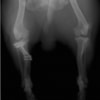

左後肢の挙上を主訴に来院されました。触診にて両関節の前方引き出し兆候、両膝蓋骨の内方脱臼を認めました。関節液検査より免疫介在性多発性関節炎は否定的でした。レントゲン検査にてfat pad signを伴う関節炎が認められたことから、前十字靭帯断裂と膝蓋骨内方脱臼(左GradeⅢ 右GradeⅢ〜IV)併発と診断し、手術を行いました。

手術は片足ずつ行い、両膝とも術中の関節鏡検査にて前十字靭帯の完全断裂と半月板損傷を確認しました。TPLO、半月板切除と滑車溝形成を始めとした膝蓋骨脱臼整復術を実施いたしました。膝蓋骨の安定化を測るために外側支帯を強固に縫合し、内側支帯は切除し縫合せずに開放状態にしています。

術後の歩行状態は良好です。

術前正面像

術後左後肢正面像

術前のTPAは左後肢33.1°右後肢26.8°でしたがTPLO実施により左後肢5.5°右後肢12°に矯正されました。